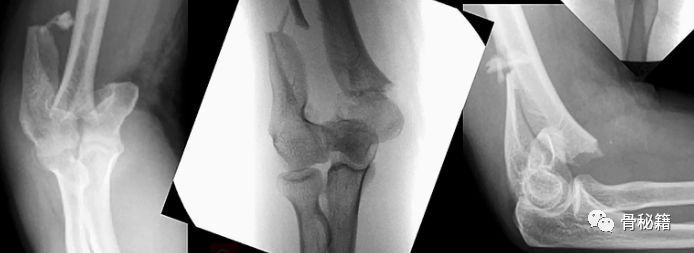

看看这些失败的case,肱骨远端不简单!